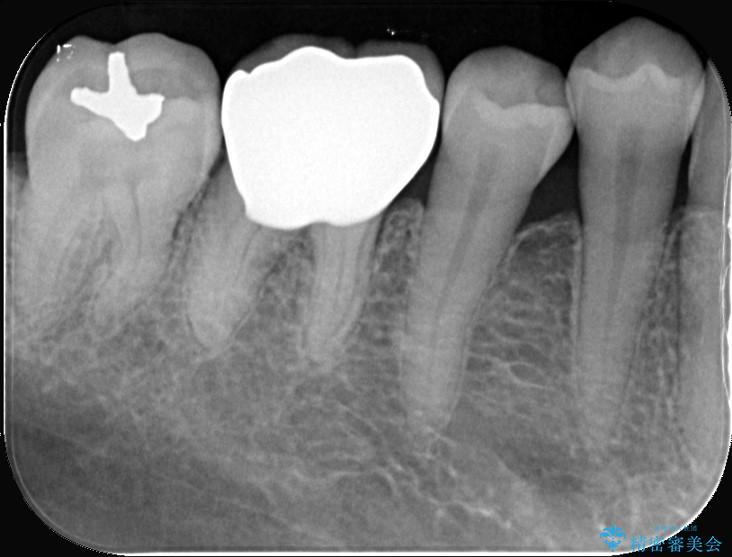

- 「銀歯を白くしたい」を主訴に来院された患者様です。銀歯を外し虫歯を除去後、オールセラミッククラウンで治療を行いました。

銀歯を外して内部の虫歯を丁寧に除去した後、オールセラミッククラウンにて修復を行いました。審美性と機能性の両面で改善が得られ、患者様にもご満足いただきました。